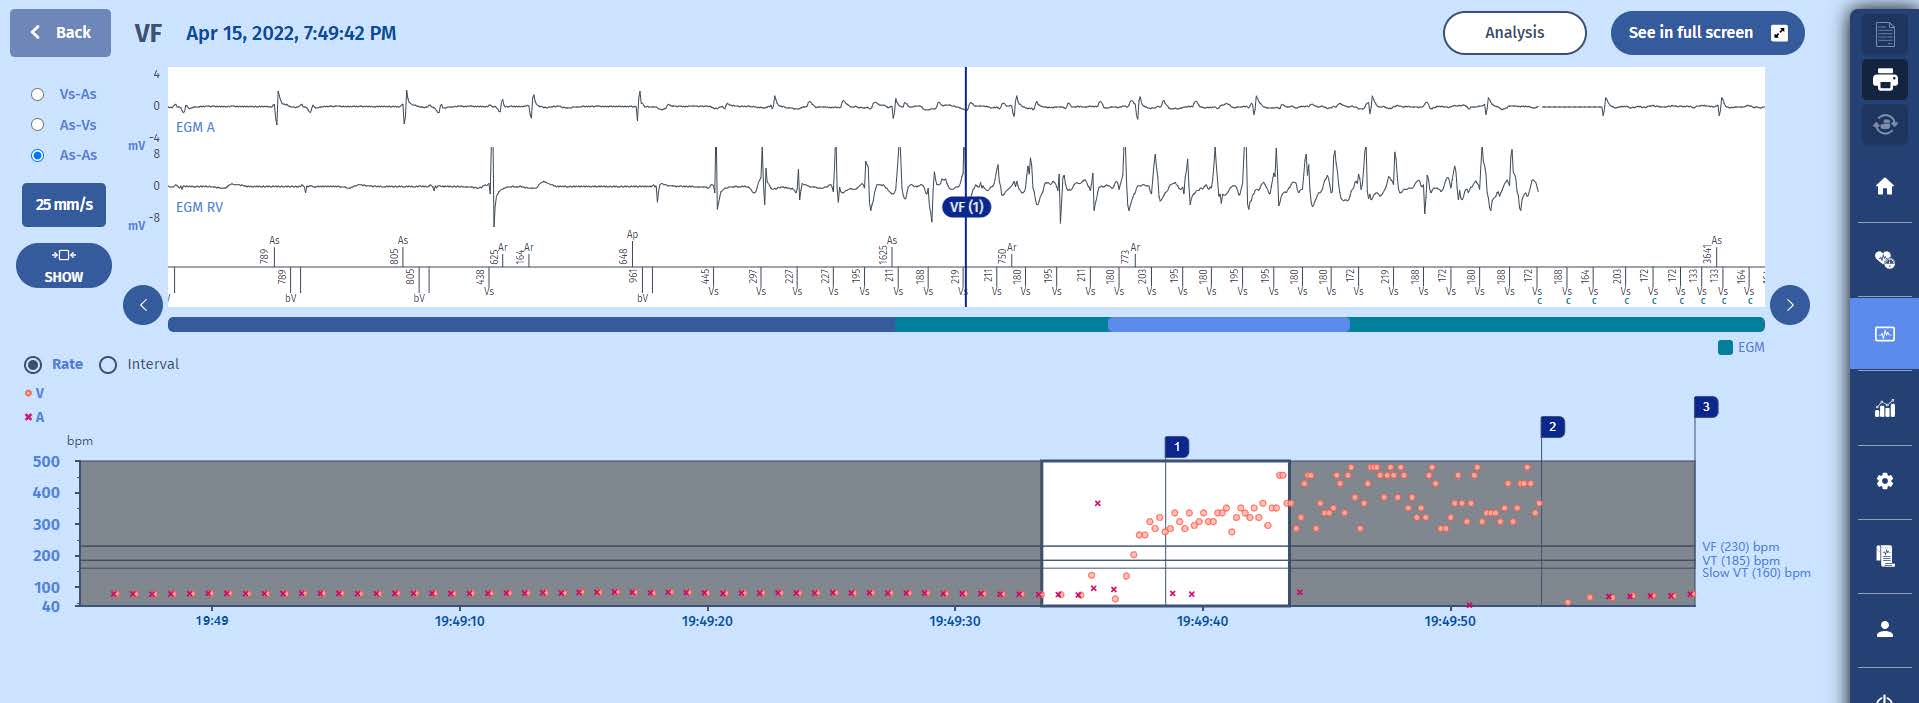

The following three screens show the episode:

EGM

1 The tracing confirms the onset of a very fast ventricular fibrillation (VF (1)) detected above 255/min at nearly 300/min, and triggering a charging of the capacitors (C markers) after a persistence of 20 cycles. The VF episode is perfectly detected.

2 Throughout the charge, the VF majority is analysed cycle-by-cycle and the charge continues as long as the VF majority does not change to SVT/ST or SR (Slow Rhythm).

3 Upon completion of the charge of the capacitors at 42 J, the shock (37.7 J) is delivered after a confirmation cycle which is also in the VF zone. The slow rhythm is restored with atrial sensing and biventricular pacing.

4 The functioning herein is a textbook case: perfect detection of all the signals, correct diagnosis, quick initiation of the therapy, effective shock, memorization of the episode